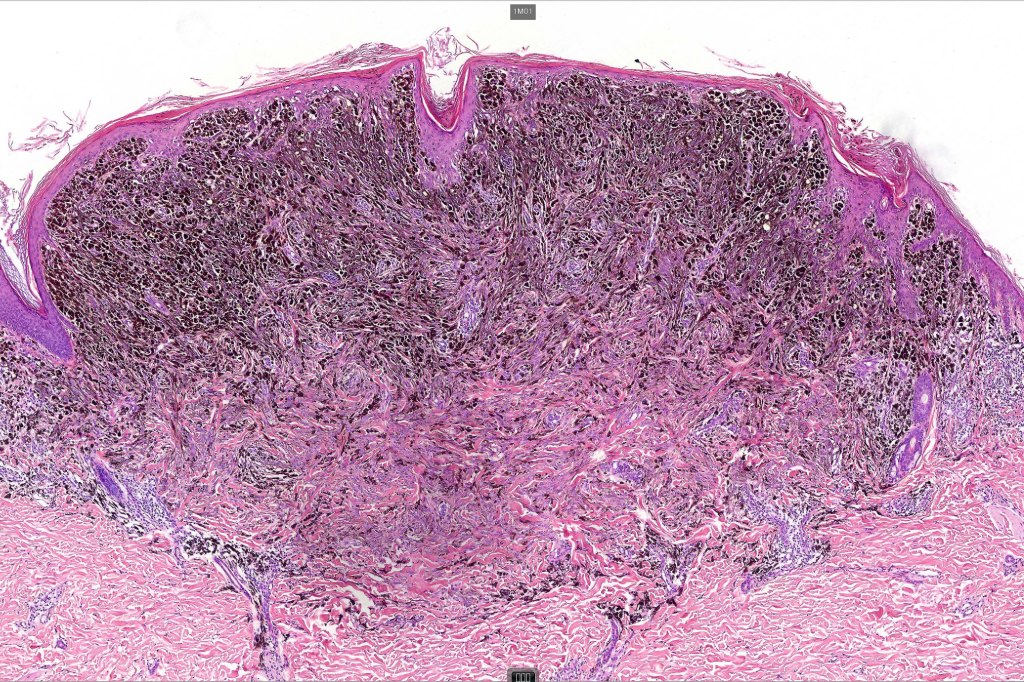

•Dermal of less often compound

•Wedge shape or less often plaque like silhouette

•Commonly associated with marked acanthosis/pseudoepitheliomatous hyperplasia although much less commonly, the epidermis is strteched over the lesion